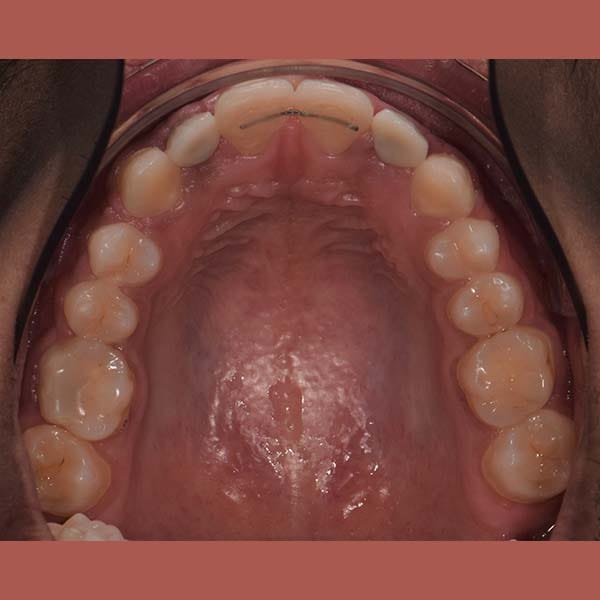

AFTER

عانت هذه السيدة من وجود عضة عميقة أمامية و غياب خلقي لسنين أماميين سفليين ،بالإضافة لتراكب و عدم ارتصاف الأسنان الأمامية العلوية بشكل جيد – تم فتح مسافة كافية لوضع غرستين سنيتين و تم تصخيح العضة العميقة تقويمياً